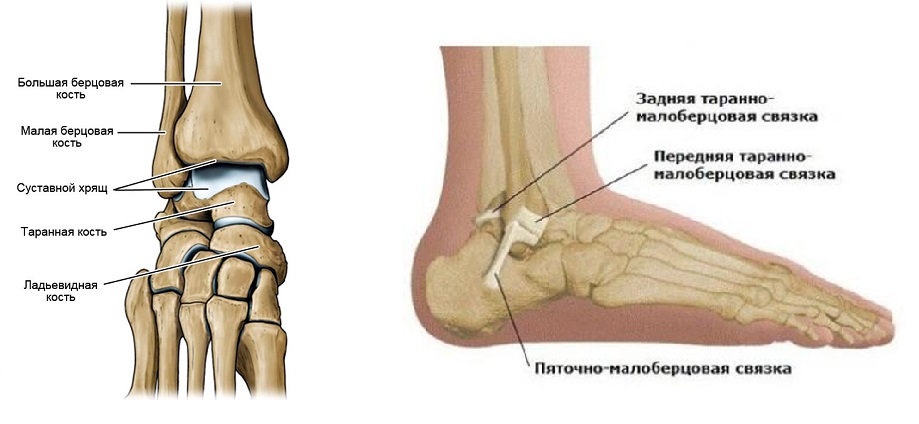

Анатомия голеностопа: Сухожилия и их строение